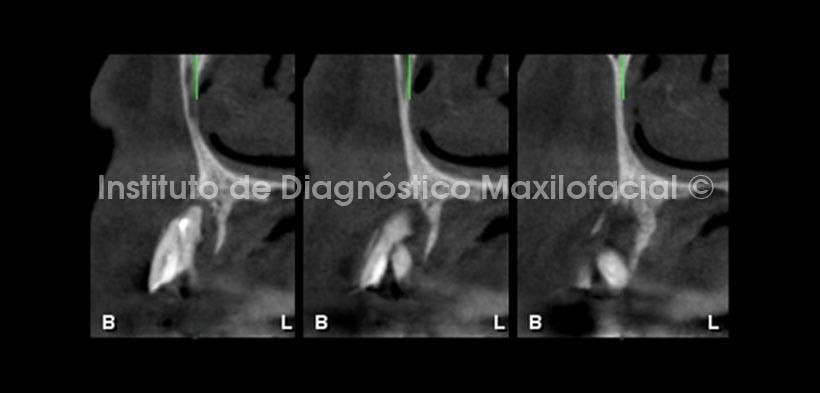

En cortes transaxiales se aprecia la marcada destrucción ósea asociada a la pieza 2.3. Nótese que la fractura no ha comprometido el ápice, sin embargo ha provocado la separación de los segmentos radiculares, así mismo se observa el marcado adelgazamiento de la tabla vestibular y palatina, condicionado por el proceso osteolítico perirradicular.